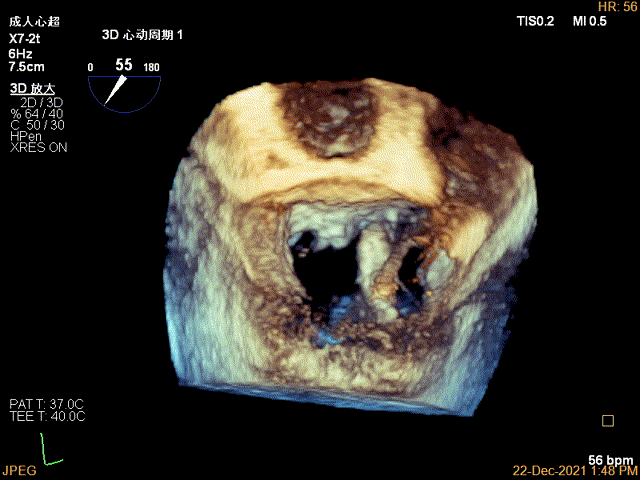

3D MV View:P2区脱垂

Qlab软件勾画估测瓣口面积约:7.19cm²

3D-VIEW验证抓捕结果

3D-color-VIEW验证残余分流近消失